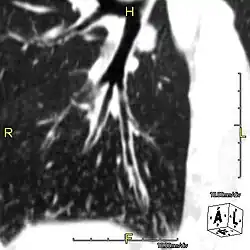

Around 80% of people with primary ciliary dyskinesia experience respiratory problems beginning within a day of birth. Many have a collapsed lobe of the lung and blood oxygen low enough to require treatment with supplemental oxygen.[1] Within the first few months of life, most develop a chronic mucus-producing cough and runny nose.[1] The main consequence of impaired ciliary function is reduced or absent mucus clearance from the lungs, and susceptibility to chronic recurrent respiratory infections, including sinusitis, bronchitis, pneumonia, and otitis media. Progressive damage to the respiratory system is common, including progressive bronchiectasis beginning in early childhood, and sinus disease (sometimes becoming severe in adults). However, diagnosis is often missed early in life despite the characteristic signs and symptoms.[2] In males, immotility of sperm can lead to infertility, although conception remains possible through the use of in vitro fertilization, there also are reported cases where sperm were able to move.[8] Trials have also shown that there is a marked reduction in fertility in females with Kartagener's syndrome due to dysfunction of the oviductal cilia.[9]

Many affected individuals experience hearing loss and show symptoms of otitis media which demonstrates variable responsiveness to the insertion of myringotomy tubes or grommets. Some patients have a poor sense of smell, which is believed to accompany high mucus production in the sinuses (although others report normal – or even acute – sensitivity to smell and taste). Clinical progression of the disease is variable, with lung transplantation required in severe cases. Susceptibility to infections can be drastically reduced by an early diagnosis. Treatment with various chest physiotherapy techniques has been observed to reduce the incidence of lung infection and to slow the progression of bronchiectasis dramatically. Aggressive treatment of sinus disease beginning at an early age is believed to slow long-term sinus damage (although this has not yet been adequately documented). Aggressive measures to enhance clearance of mucus, prevent respiratory infections, and treat bacterial superinfections have been observed to slow lung-disease progression. The predicted incidence is 1 in approximately 7500.[10]